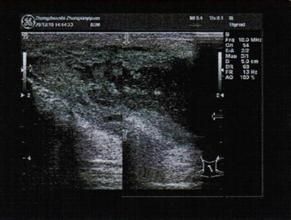

2、血管分布CDI顯示血管管腔內的血流,因而屬於流道型顯示,它不能顯示血管壁及外膜。

3、鑑別癌結節的血管種類用CDI可對肝癌結節的血管進行分類。區分其為結節周圍繞血管、給節內緣弧形血管。結節的流人血管、結節內部血管及結節流出血管等。